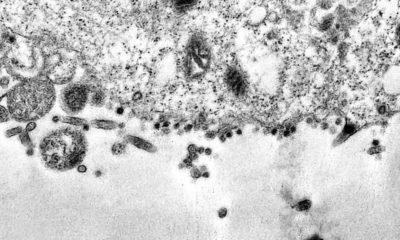

Entre junho e julho, os casos de covid-19 causados pela variante delta do Sars-Cov-2, surgida na Índia, avançaram no estado do Rio de Janeiro e já...

Até ontem (3), 28 novas amostras da variante delta do novo coronavírus foram confirmadas na capital de São Paulo. O monitoramento ativo da prefeitura, em parceria...